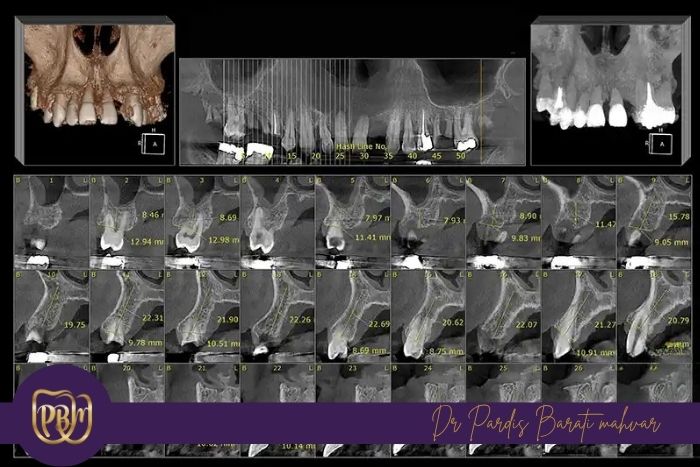

ضخامت استخوان: باید حداقل 6 تا 7 میلیمتر باشد تا بدنه ایمپلنت بهطور کامل در استخوان قرار گیرد. این مقدار به این معناست که استخوان باید آنقدر پهن باشد که دیوارههای دو طرف ایمپلنت را کاملاً در بر بگیرد، در غیر این صورت خطر نفوذ ایمپلنت به بیرون از استخوان یا تخریب بافت وجود دارد.

ارتفاع: باید حداقل 10 تا 12 میلیمتر باشد تا پایه ایمپلنت فاصلهای از اعصاب و حفره سینوس داشته باشد. اگر ارتفاع کمتر باشد ممکن است پایه ایمپلنت به عصب فک پایین فشار وارد کند یا به سینوس فک بالا نفوذ کند که میتواند درد، بیحسی یا عفونت ایجاد کند.